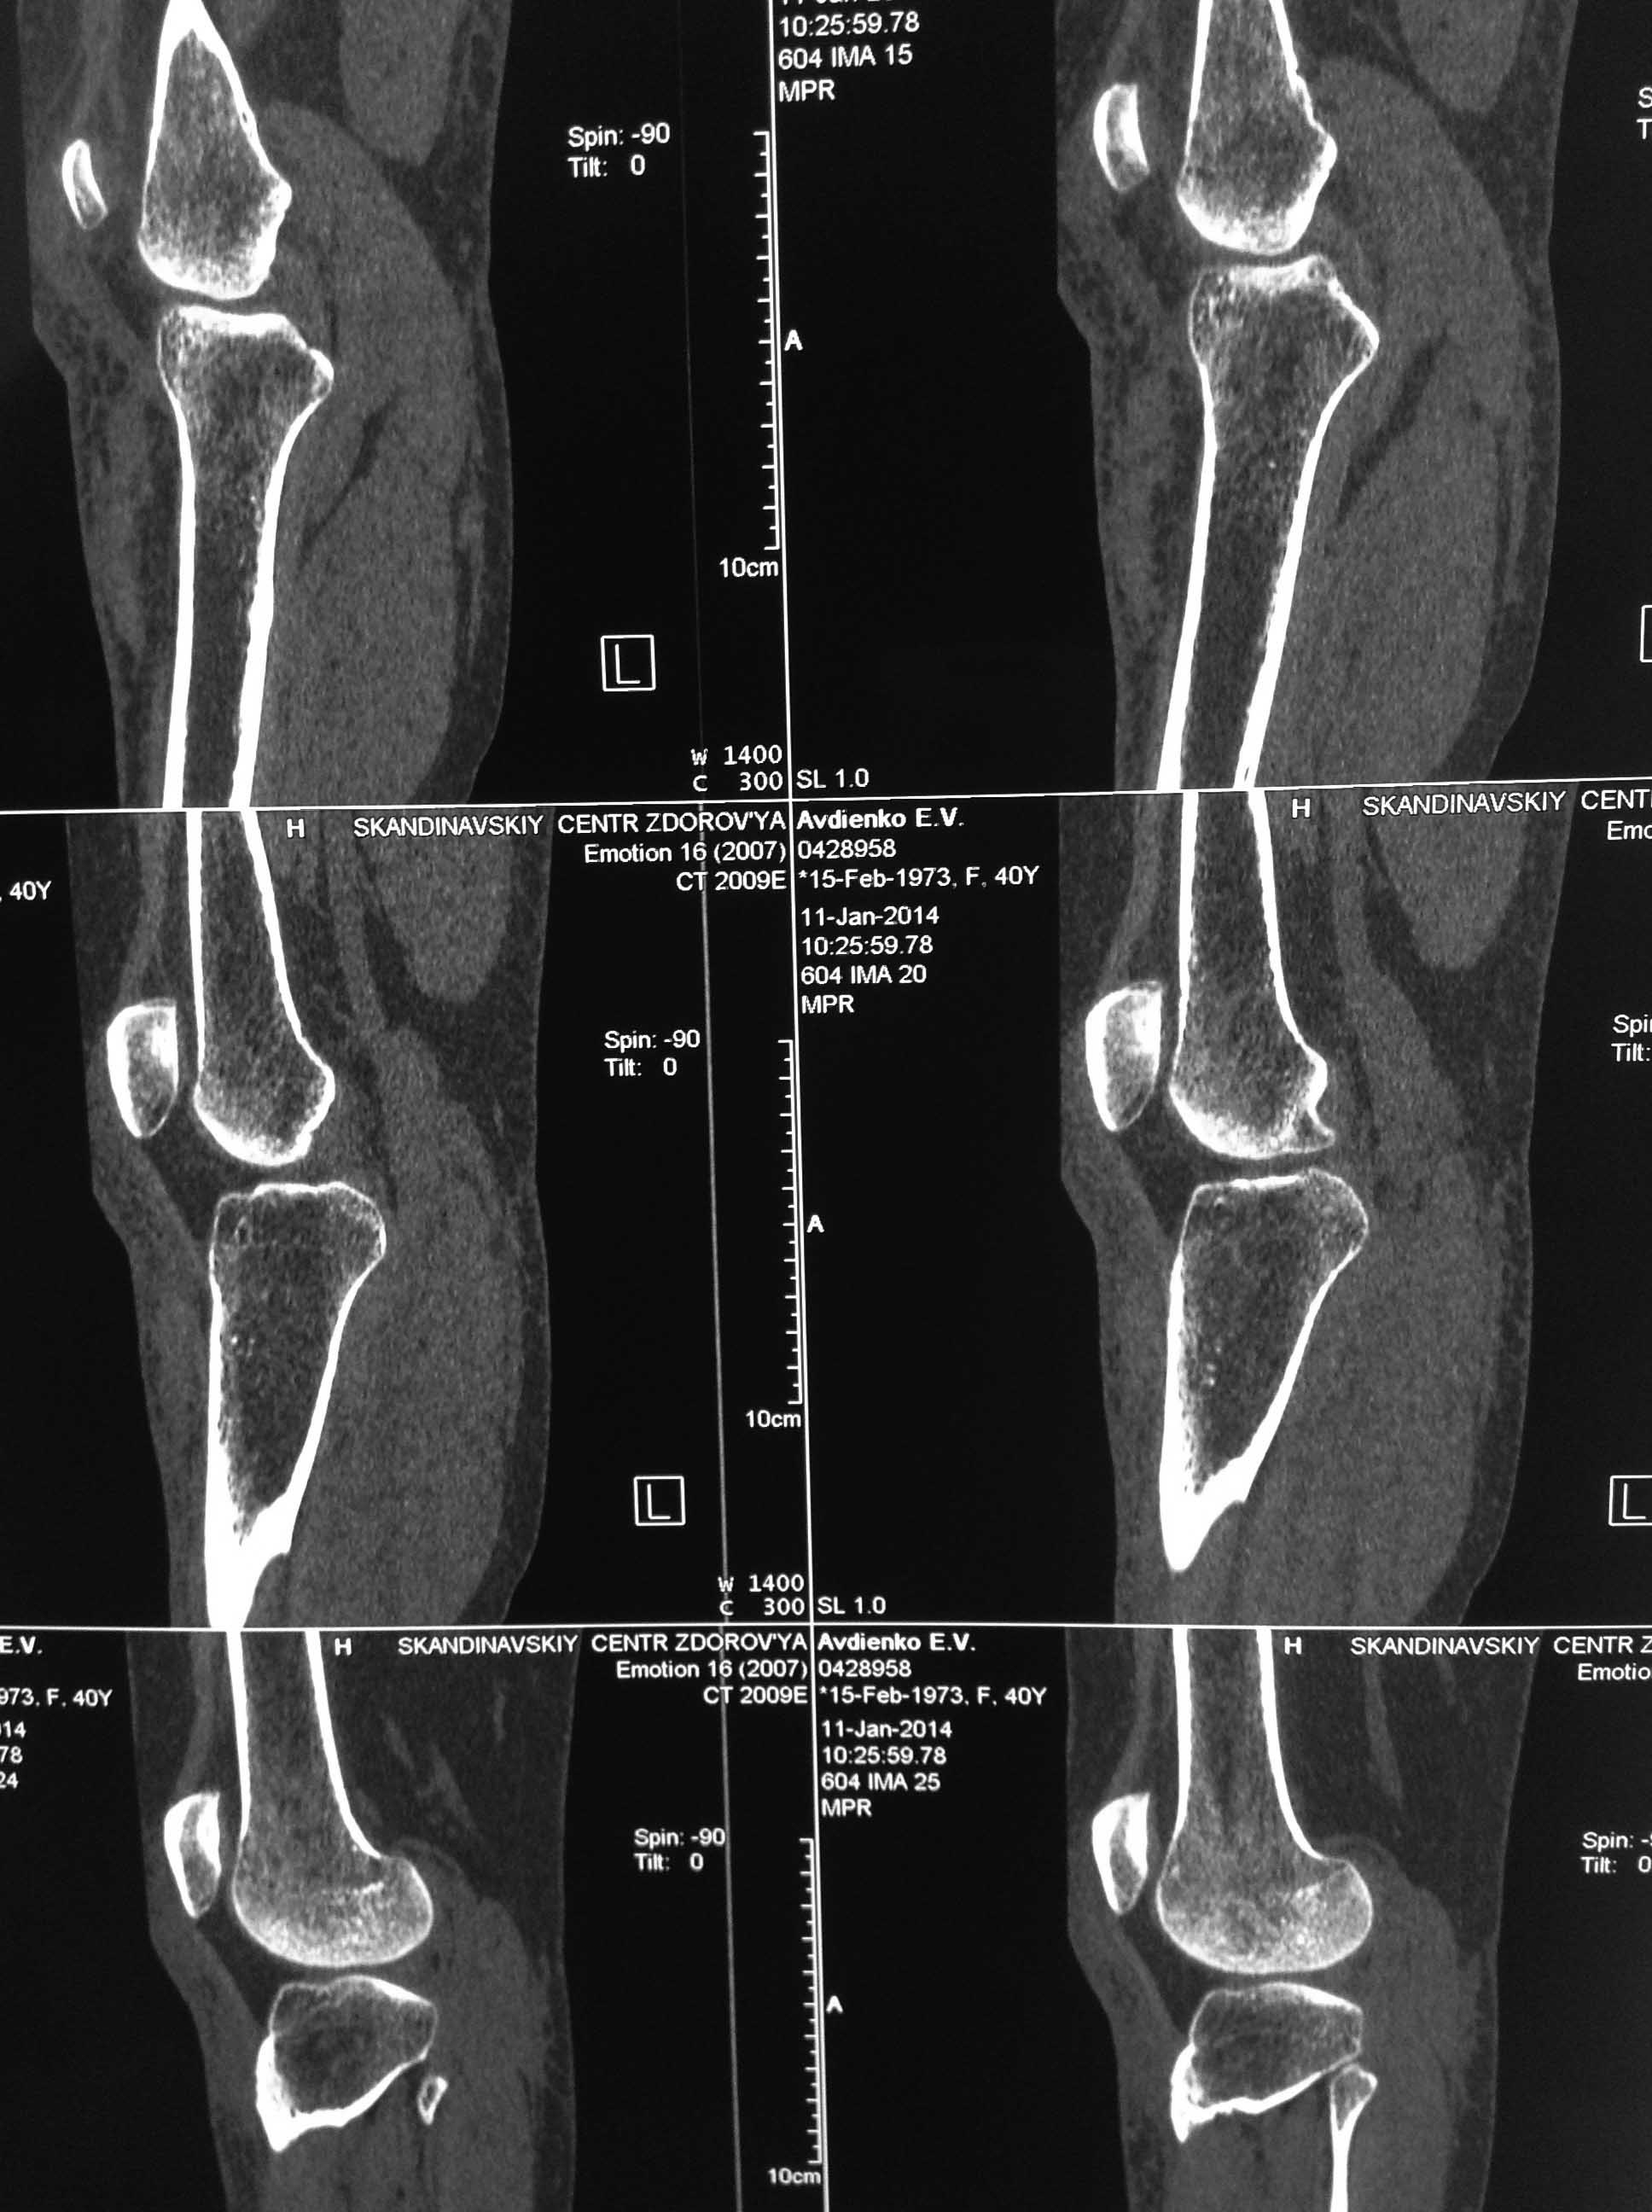

Уважаемые коллеги? Понимаю несуразность поста, но все же. Пациентка Ж 40 лет, травма ДТП 29.12.13, по месту получения травмы вскрыта межмышечная гематома, иммобилизация тутором.

Объективо- движения в коленном суставе 0/0/0, связочный аппарат стабилен. НО САМОЕ консультация профессора ( дама не из простой семьи) - и вердикт - оскольчатый внутри суставной перелом наружного мыщелка большеберцовой кости и лечение- 3 месяца постоянный тутор. Меня чуть на ноль не умножали, что я пропустил перелом в таком важном месте. Коллеги!!!!!! А был ли мальчик, вглядитесь пожалуйста и вынести решение!!!!!!!

1. Перелома не видно

2. Если продолжать спорить, то нужно РКТ а не МРТ, и, согласен, лучше артроскопия.

Импрессионного,тем более оскольчатого, перелома наружного мыщелка нет.